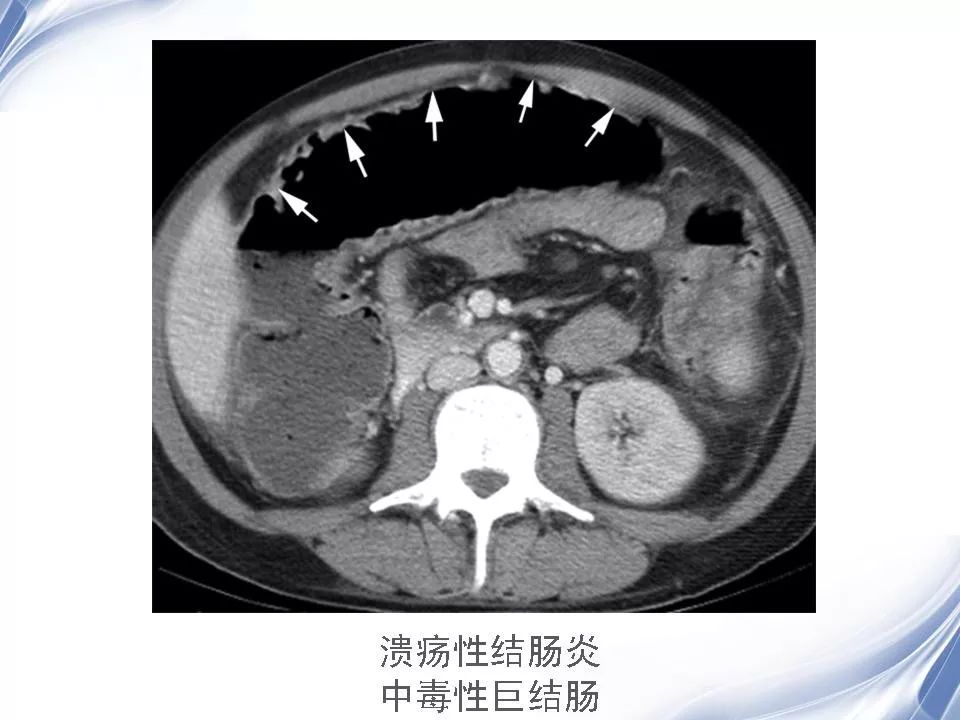

炎症性肠病的ct诊断影像天地

图片尺寸960x720

溃疡性结肠炎